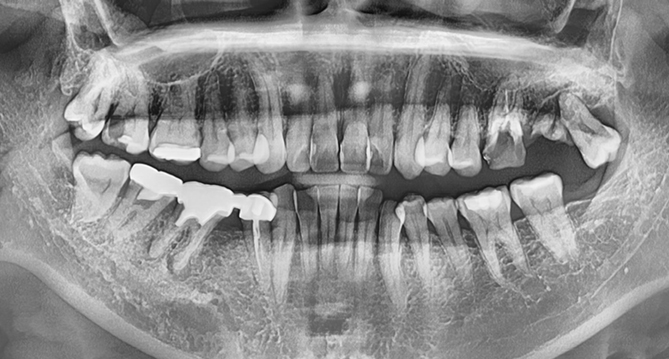

연세새빛치과 상악동거상임플란트 사례

연세새빛치과 전악 임플란트 사례